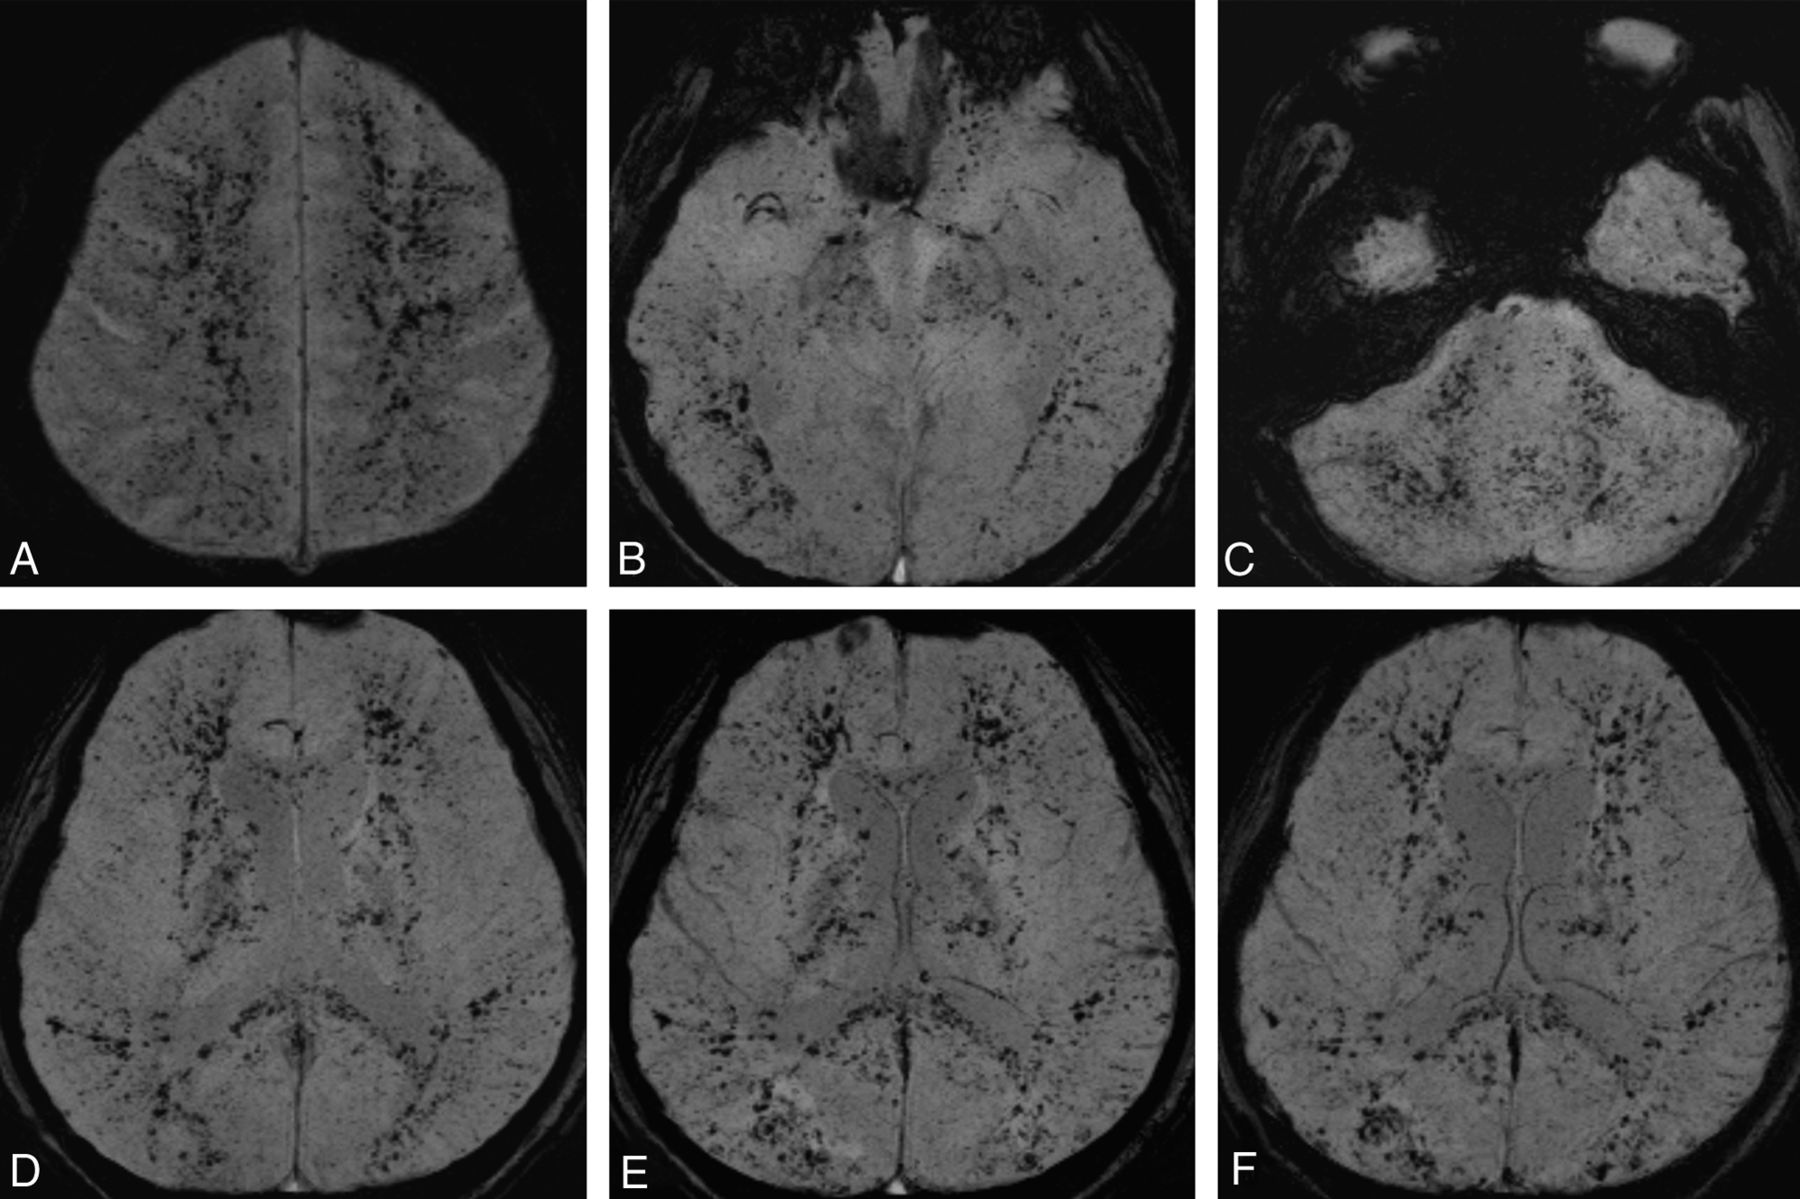

Type 2C: Petechial Hemorrhage of White Matter

T2* sequences, such as gradient-echo images or SWI, are sensitive for detecting vascular structures, blood products, and changes in iron content. Previous reports have mentioned that it is common to detect tiny petechial hemorrhages of the perivascular space in CFE.3,7⇓–9 Suh et al3 mentioned that SWI is better at detecting hemorrhages of CFE than gradient-echo images. In this review, the type 2C pattern was noted in all stages (60%, 60%, and 88% in acute, subacute, and late stages, respectively; Fig 2). Petechiae were noticed as early as the first day of the long bone fracture and could last through the whole course without significant change (Fig 5). Differential diagnoses included diffuse axonal injury, which presents with petechial hemorrhage as well. However, diffuse axonal injury mainly occurs in the gray-white matter interface of the frontotemporal lobes and corpus callosum, while CFE petechial hemorrhage is located predominantly in the white matter and shares the same distribution as the confluent white matter cytotoxic edema pattern (type 2A). In our opinion, the high positive rate with early-onset and persistent, specific MR imaging characteristics indicating petechiae hemorrhage and unique distribution in white matter could make this pattern a pathognomonic feature of CFE.

Serial axial SWI images of the second case at postfracture week 3 (A–D) demonstrate numerous petechial hemorrhages in the subcortical and periventricular white matter, cerebellar hemisphere and peduncle, and posterior corpus callosum bilaterally. Corresponding images of the same level at postfracture week 5 (E) and 3 months (F) demonstrate no significant interval change (type 2C pattern).